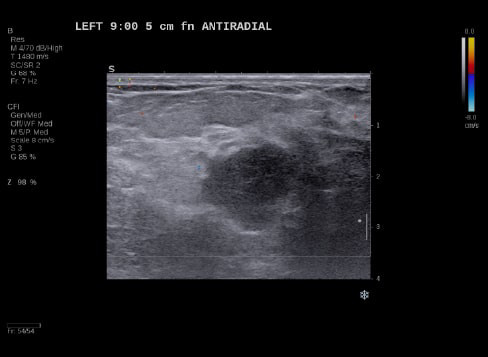

Case Example 5:

59-year-old female presents with a new mammographic asymmetry on the left breast.

A 1.2 cm mass is seen on ultrasound with some doppler signal along periphery of mass.

Case Example 5: Observations

With OA imaging we can see negative internal findings but positive external features in the boundary and peripheral zones.

We can see feeding and draining vessels or “whiskers” in the boundary and peripheral zones on OA.

Radiating vessels continue from the peripheral zone into the boundary zone and count as features in both zones.

Invasive Ductal Carcinoma Grade I

- ER+

- HER2-

- PR-

- Ki67=10%

The mass was up-classified to BI-RADS 5. Unlike TNC, luminal A masses typically present with external features in the boundary and peripheral zones and no OA internal features. Typically, luminal A masses have a low Ki67 and tend to have less internal angiogenesis and deoxygenation.